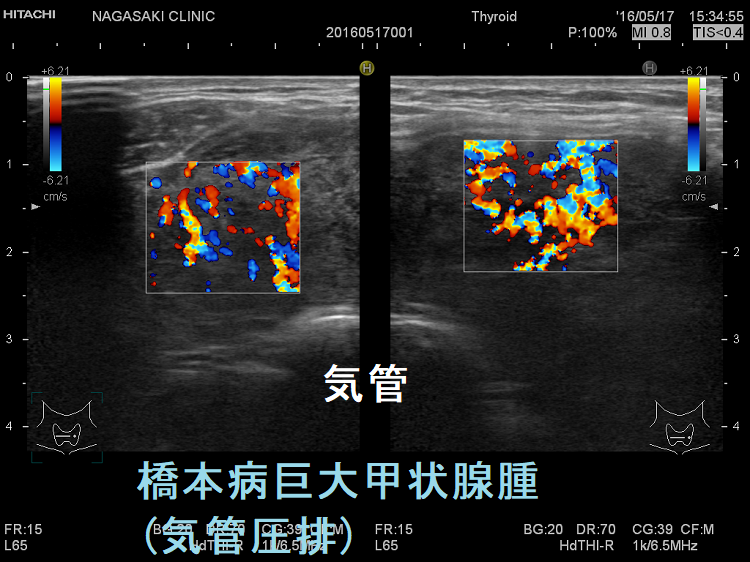

橋本病などの巨大甲状腺腫

海外では、閉塞性睡眠時無呼吸症候群(OSAS)治療のために、肥満者あるいは非肥満者の巨大甲状腺腫を摘出して改善を認めた論文があります(Monaldi Arch Chest Dis. 2006 Mar;65(1):52-5.)(World J Surg. 2014 Aug;38(8):1990-4.)。

しかし、日本では、腫瘍もない甲状腺を閉塞性睡眠時無呼吸症候群(OSAS)治療のために全摘出するのは難しいと思います。(甲状腺外科が納得しないでしょう)